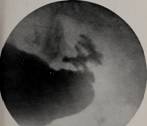

Text Appearing Before Image:

Fig. 13. Case 154564. Roentgenogram. Niche-type ofulcer,

benign. Arrow points to niche. Compare withFigure 14.

Fig. 15. Case 20799. Roentgenogram. Niche-type ofulcer.

Niche extraordinarily large. Operation. Can-cer

demonstrated microscopically.

Text Appearing After Image:

Fig. 14. Case 116521. Roentgenogram. Niche-type ofulcer,

malignant. Arrow points to niche. BIBLIOGRAPHY 1. .\ii\Mi,